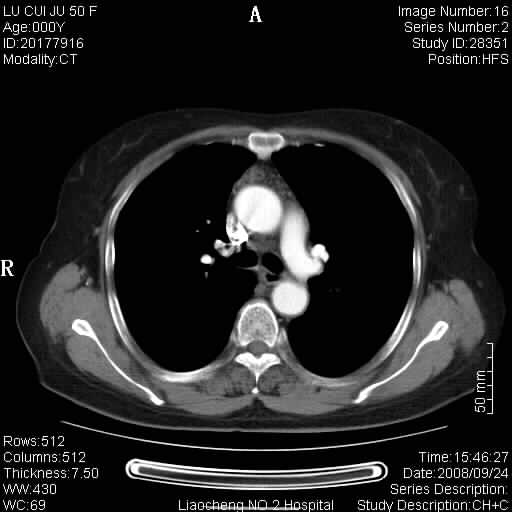

标题: CT15870:F50Y,纵膈占位,是不是胸腺瘤,请各位高手讨论。

临床表现为重症肌无力;ct增强扫描可见前纵膈胸腺部位弥漫性簇状软组织节结灶,不知道是不是胸腺瘤,请各位高手讨论。

胸腺外缘稍向外突,未见确切占位改变。结合临床考虑胸腺增生可能性大。

考虑胸腺增生!!

胸腺组织残留